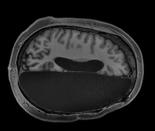

感情の対立 8月22日、グラウンド・ゼロ周辺はモスク建設反対派と賛成派のデモ隊で埋め尽くされた Jessica Rinaldi-Reuters